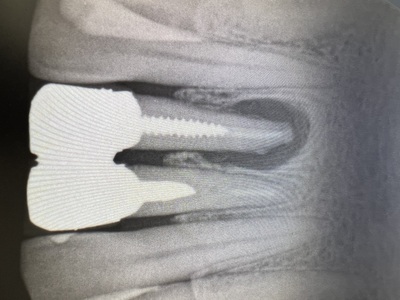

左から右へインプラントオペの流れ。

image003.jpg

<<写真が鮮明でなく歪みがあるのは、モニターをそのままスマホで撮影しているため>>